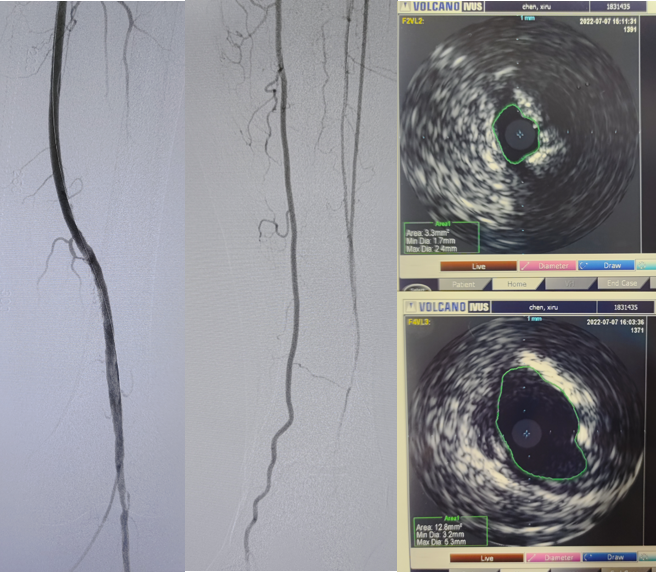

病例2(股腘动脉长段闭塞):

另一例长段闭塞病变,IVUS证实导丝真腔通过后,指导术者选择了合适尺寸的Rotarex导管进行减容,联合普通球囊(POBA)预扩及DCB治疗,获得了满意的管腔,避免了支架植入。